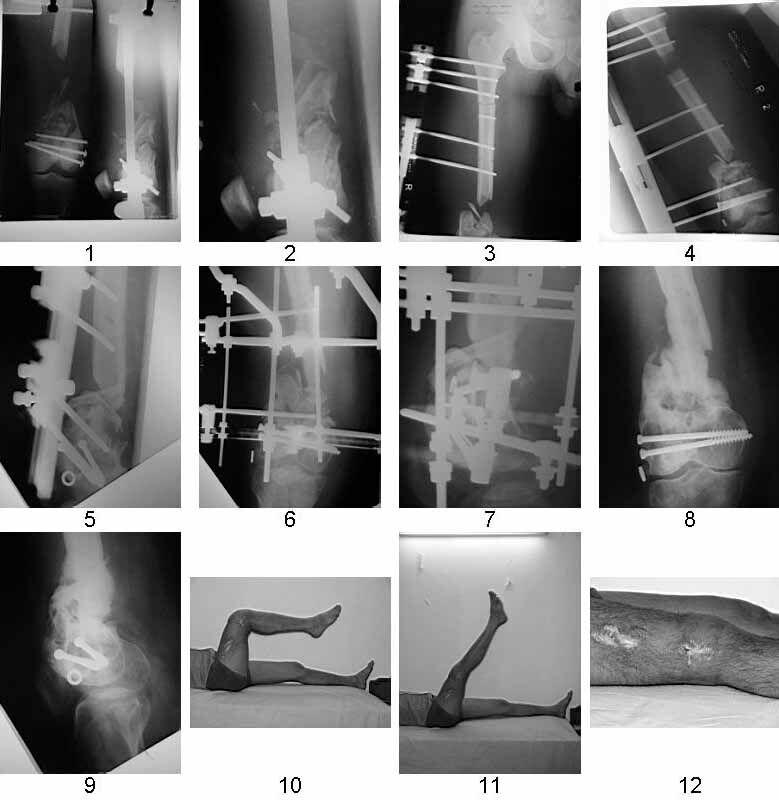

dear MAGDY we have treated exactly similar case intially with debridement & ILIZAROV ring fixator by end of three months patient had exuberent callus along whole length of left out periosteal sleeve &fixator was removed walking spica was applied, unfortunately after one month in spica he developed break in the bridging bone and now we have treated him with locking plate &bone graft one month back and on CPM machine with knee movement of 90 deg.

Similar case.

They do well with bone transport.

I do an acute or accelerated shortening to reduce the gap as much as proximal, and distract proximally to restore length.

In this particular case, notice the change of fixator - orthofix type of unilateral fixator worked well initially but did not allow me to compress beyond a point, which is when I changed to an ilizarov for further compression at the gap/nonunion site.

Mangal Parihar